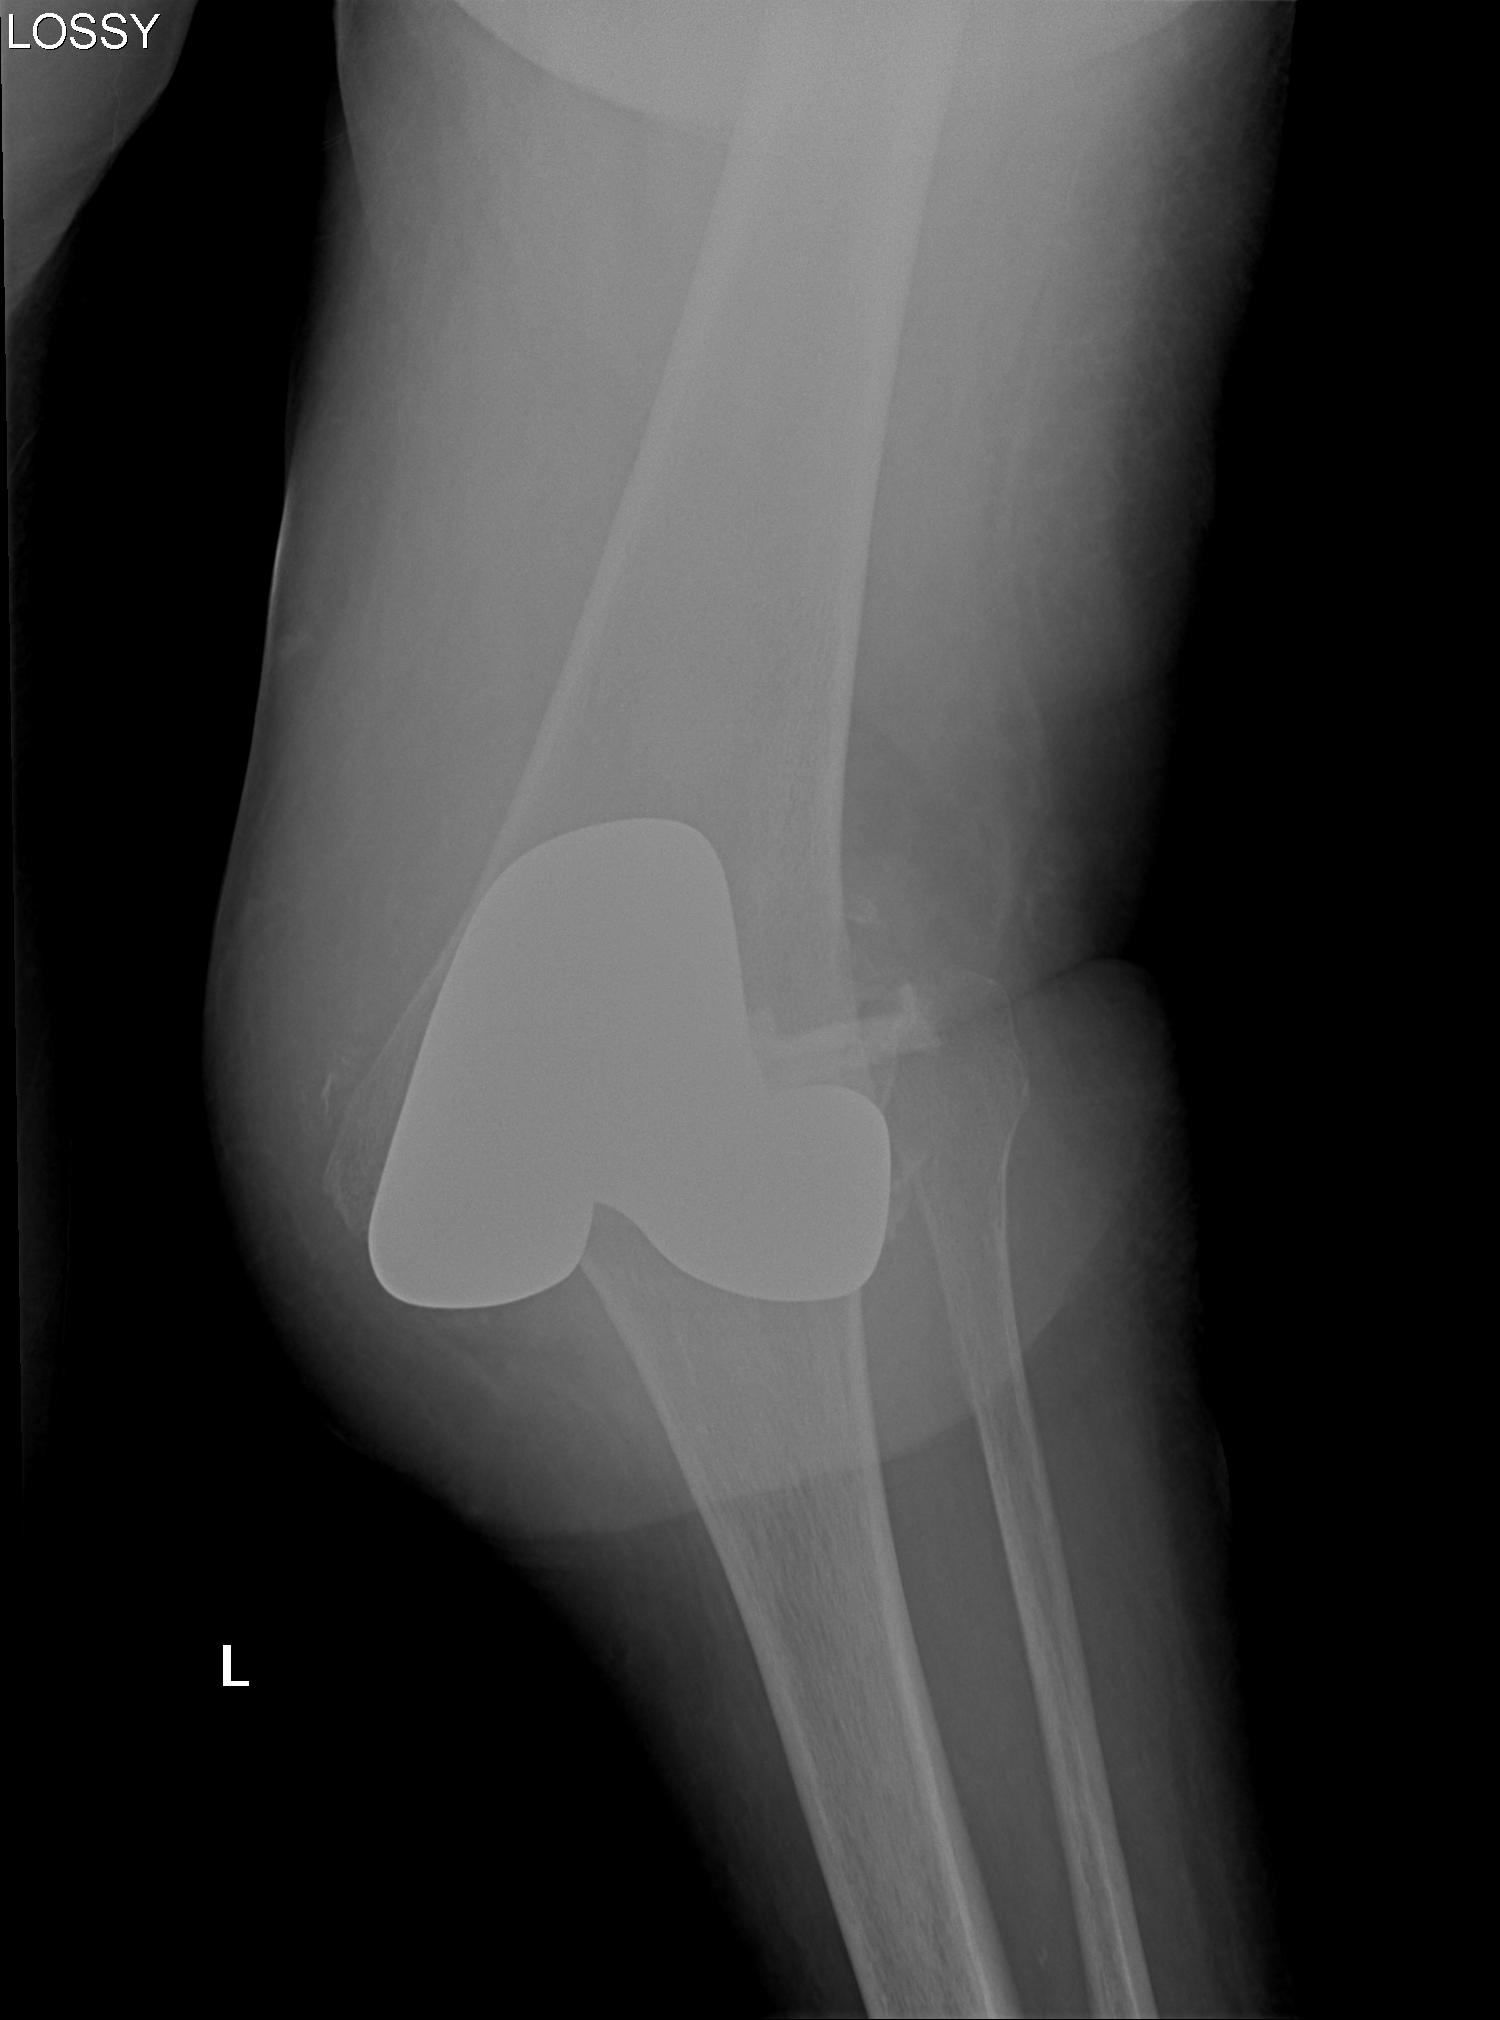

1. AP Instability

2. Varus Valgus Instability

3. Global Instability

4. Frank Dislocation